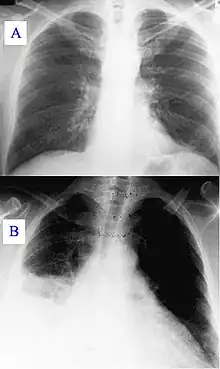

| Pneumonia as seen on chest X-ray. A: Normal chest X-ray. B: Abnormal chest X-ray with consolidation from pneumonia in the right lung, middle or inferior lobe (white area, left side of image). | |

- Typically, an area of white lung is seen on a standard X-ray.[5] Consolidated tissue is more radio-opaque than normally aerated lung parenchyma, so that it is clearly demonstrable in radiography and on CT scans. Consolidation is often a middle-to-late stage feature/complication in pulmonary infections.